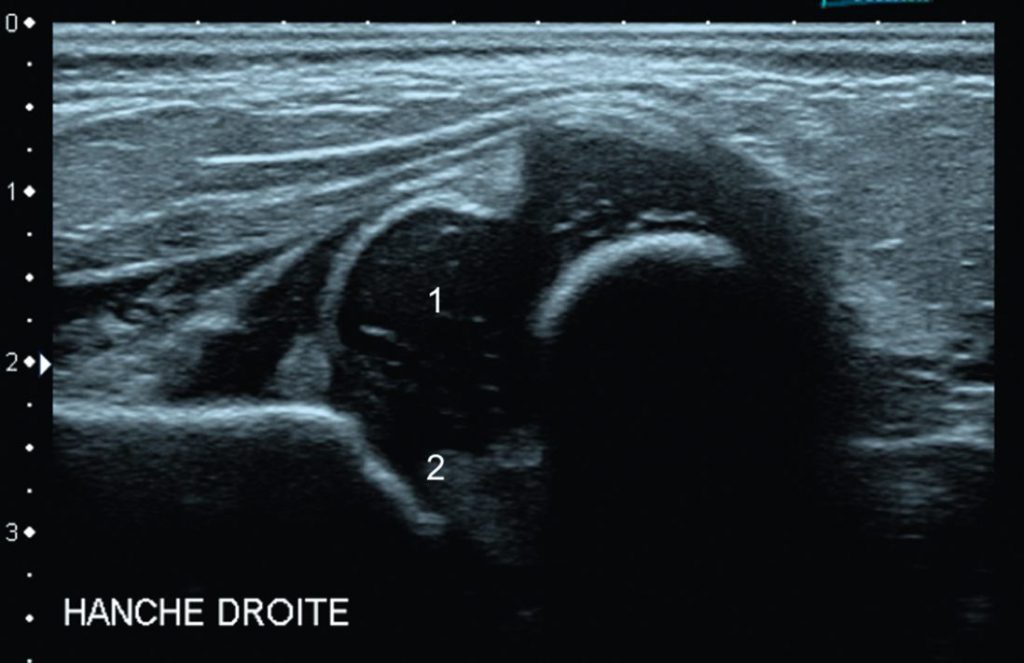

Fig. 116.2 Échographie de hanche. Coupe frontale d’un enfant présentant une manœuvre d’Ortolani positive, avec ressaut lors de la mise en abduction de la hanche.

Il existe une luxation complète de la tête fémorale (1) qui se projette en dehors de la cavité cotyloïdienne (2).

Source : CERF, CNEBMN, 2022.